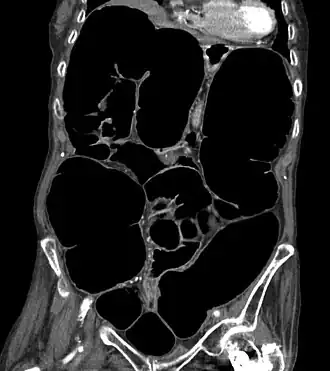

A pseudo-obstrução colônica aguda é caracterizada pela dilatação maciça do ceco (diâmetro maior a 10 cm) e cólon direito na radiografia abdominal. Se não for descomprimido, o paciente corre o risco de uma isquemia intestinal, perfuração intestinal e peritonite com taxa de mortalidade de até 40%. É um tipo de megacólon, por vezes referido como "megacólon agudo", para distingui-lo do megacólon tóxico.

O diagnóstico começa com o exame físico, observação e entrevista do paciente. Imagens para diagnosticar a dilatação do cólon e descartar causas de obstrução (Póstero-anterior abdominal ereto e abdômen supino). Se mais imagens forem necessárias, uma TC pode ser solicitada.